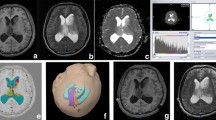

Fifty-six patients with radiologically suspected untreated glioma were studied with T1- and T2-weighted MR imaging, dynamic contrast-enhanced MR imaging, diffusion tensor imaging, and volumetric whole-brain MR spectroscopic imaging. Receiver-operating characteristic analysis was performed using the relative cerebral blood volume (rCBV), apparent diffusion coefficient, fractional anisotropy, and multiple spectroscopic parameters to determine optimum thresholds for tumor grading and to obtain the sensitivity, specificity, and positive and negative predictive values for identifying high-grade gliomas. Logistic regression was performed to analyze all the parameters together.

The rCBV individually classified glioma as low and high grade with a sensitivity and specificity of 100 and 88 %, respectively, based on a threshold value of 3.34. On combining all parameters under consideration, the classification was achieved with 2 % error and sensitivity and specificity of 100 and 96 %, respectively.